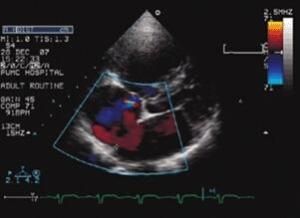

採用偽彩色編碼技術,多用紅=藍色的代表血流的向背方向。顏色的深淺,代表血流的快慢,通稱彩色都卜勒超聲,簡稱CDFI(ColorDopplerflowimaging)。

一、彩色都卜勒超聲一般是用自相關技術進行都卜勒信號處理,把自相關技術獲得的血流信號經彩色編碼後實時地疊加在二維圖像上,即形成彩色都卜勒超聲血流圖像。由此可見,彩色都卜勒超聲(即彩超)既具有二維超聲結構圖像的優點,又同時提供了血流動力學的豐富信息,實際套用受到了廣泛的重視和歡迎,在臨床上被譽為“非創傷性血管造影”。

1、血流方向,在頻譜都卜勒顯示中,以零基線區分血流方向。在零基線上方者示血流流向探頭,零基線以下者示血流離開探頭。在CDI中,以彩色編碼表示血流方問,紅色或黃色色譜表示血流流向探頭(熱色);而以藍色或藍綠色色譜表示血流流離探頭(冷色)。